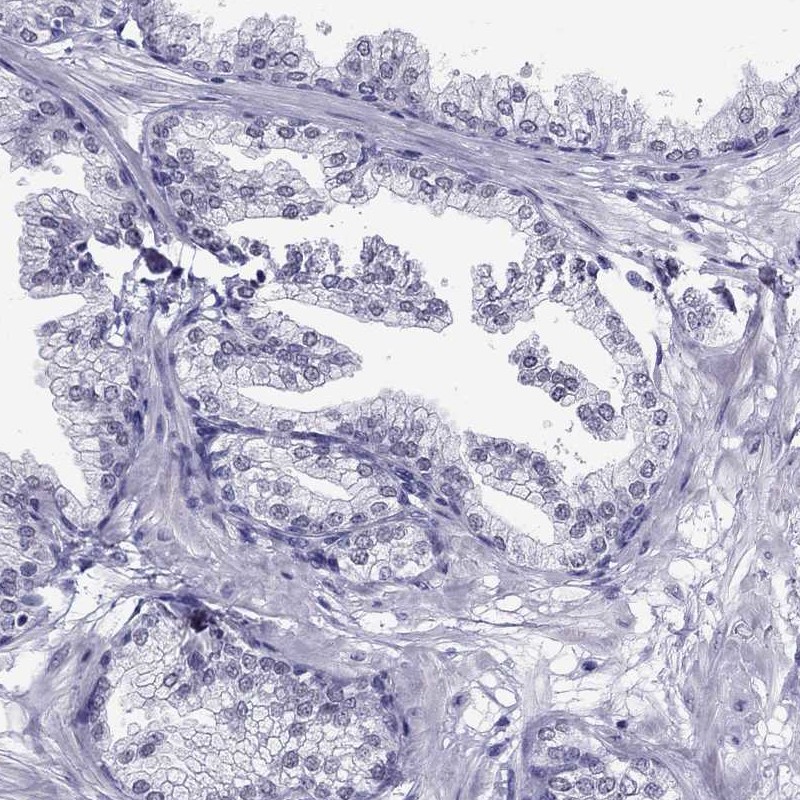

Immunohistochemistry analysis in human fallopian tube and prostate tissues using Anti-CROCC2 antibody. Corresponding CROCC2 RNA-seq data are presented for the same tissues.